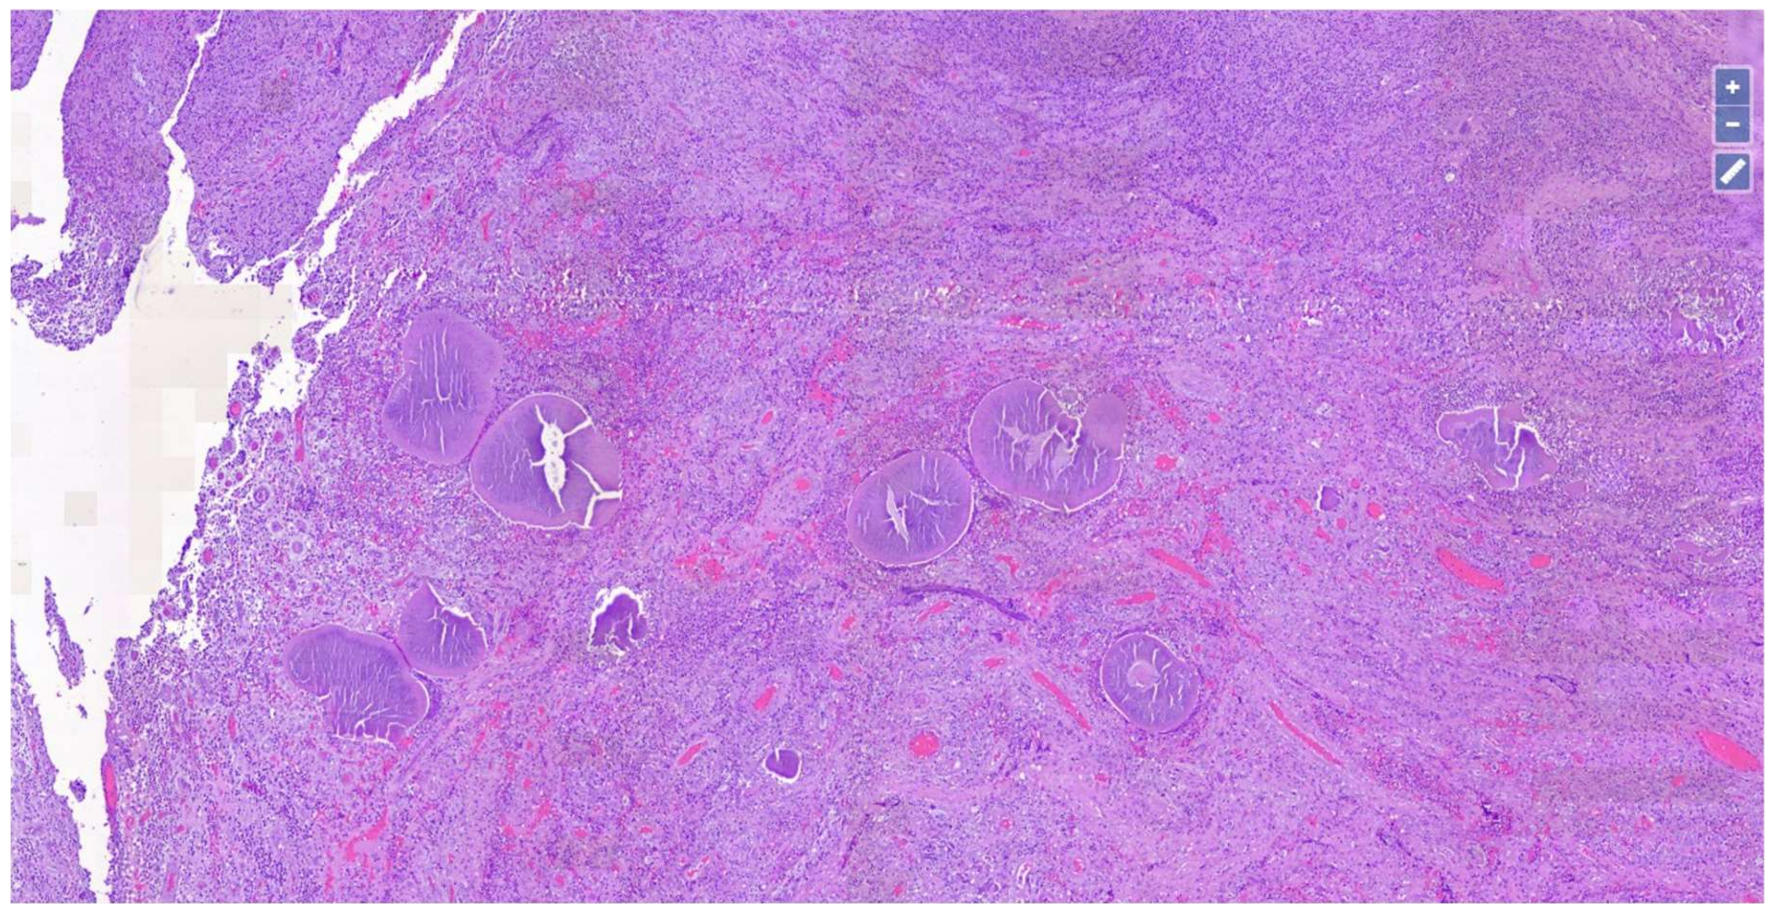

Skin Mycetoma in an 11-Year-Old African Boy: Case Presentation with Emphasis on Histopathological Features and Differential Diagnosis

2. Case Presentation